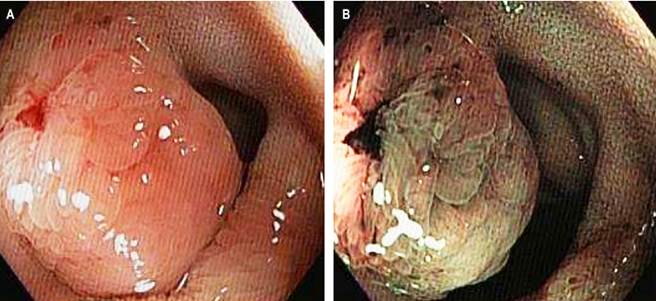

This is a 56-year-old female patient with a history of difficult-to-manage hypertension (HTN) since 2022. In the search for the origin of the HTN, she underwent various studies: a normal total abdominal ultrasound, an abdominal and pelvic MRI with contrast, which revealed pancreatic cysts, and an endoscopic ultrasound with biopsy, which provided a histological diagnosis of mucinous pancreatic cysts. She was referred to gastroenterology due to diffuse colicky abdominal pain associated with bloating and two soft stools per day, which had been present for two years. A colonoscopy with ileal intubation was performed, revealing a 15 mm sessile polypoid elevated lesion in the distal ileum, 5 cm from the ileocecal valve (Figure 1). The pathology report from the lesion biopsies showed the presence of a well-differentiated, low-grade NET (Grade I), with a mitotic count of 0-1 per mm2, CKAE1/AE3: positive, focal, extranodal extension, and strong positivity for synaptophysin, chromogranin, and enolase (Figure 2).

Figure 1 Ileocolonoscopy. Sessile polypoid lesion (Paris classification: 0-Is) in the distal ileum. A. Image with white light. B. Image with digital chromoendoscopy. Images property of the authors.